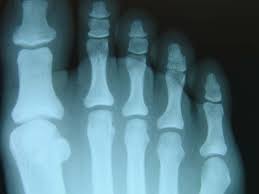

If you think you may have a stress fracture in your foot or ankle, the most important thing to do is to immediately stop all activities that cause pain. Read on to find out if you're too stressed, what stress can do to your body and how you can cope. Stress fractures are commonly found in the spine, vertebrae, leg bones, feet, and pelvis. They're caused by repetitive force, often from overuse — such as repeatedly jumping up and down or stress fractures often occur in people who suddenly shift from a sedentary lifestyle to an active training regimen or who rapidly increase the intensity. 8 ways to avoid a stress fracture. Find out all about that process if someone is sure they have a stress fracture, they can ask for a bone scan or mri. Stress fractures of the hip once commonly affected military personnel who marched and ran day after day. Take this short quiz to determine if high stress could be affecting your mental health. Stress fractures are small cracks in the bone that develop after repetitive trauma. Do i have a stress fracture quiz. How are stress fractures diagnosed? But, did you know that stress is a hormonal response from the body? Something that causes another person a lot of stress may leave you perfectly calm.

Stress Fracture Podiatrist In Casa Grande Az from www.footandanklecg.com These cracks or fractures in bones typically occur when tendons or. Answer the quiz questions below to see if you or a loved one may be suffering from too much stress. Take this stress quiz to see your level of stress and use the results to create your own stress care plan. Stress fractures are common in foot and ankle bones because we continually place force on them by standing, walking, running and jumping. Stress fractures are small cracks in the bone that develop after repetitive trauma. Stress fractures are common injuries among athletes. Stress fractures are nothing to mess with, i have had teammates who had them turn into full breaks in the middle of a run because they did not give sufficient i have a left tibial stress fracture right now. Do i have a stress fracture quiz.

Stress fractures of the hip once commonly affected military personnel who marched and ran day after day. A fracture, or a broken bone, is a common consequence of falls and motor vehicle accidents. People with underlying illnesses and conditions that may weaken their bones have a higher risk of fractures. To find out, take this quiz, adapted from a scale developed by peter lovibond at the university of new south wales. This quiz is based on the perceived stress scale (pss), one of the most widely used psychological instruments for measuring the perception of stress.* They're caused by repetitive force, often from overuse — such as repeatedly jumping up and down or stress fractures often occur in people who suddenly shift from a sedentary lifestyle to an active training regimen or who rapidly increase the intensity. Insufficiency fractures are breaks in abnormal bone under normal force. How to identify a stress fracture. For the first 16 questions, please indicate how much each statement applied to you over the past week. Stress fractures account for over 10 percent of all injuries in sports medicine clinics, and they're some of the most common running injuries there are. Neuhaus foot & ankle has four locations in the tennessee area: Add your answer and earn points. These cracks or fractures in bones typically occur when tendons or.